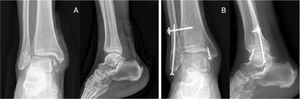

When there is a forced inversion movement, these ligaments tear from the fibula with subsequent instability of the talus within the ankle mortise. This avulsed fragment, with the inserted ligaments, has hypermobility that ultimately increases the space between the fibula and the fragment, increasing the risk of pseudoarthrosis and chronicity of this injury. Haraguchi et al.23 found 35% pseudarthrosis in patients with avulsions treated conservatively. They observed a large retraction of the fragment due to the traction exerted by the ligaments, which resulted in further separation of the fragment from the fibula.23 Therefore, surgery is a viable, reproducible option with good postoperative results. Available procedures include removal of the bone fragment and re-anchoring of the ligaments, synthesis of the fragment with compression plates and/or screws, or anatomical reconstruction plasties in cases of chronic instability18,23 (Fig. 2).